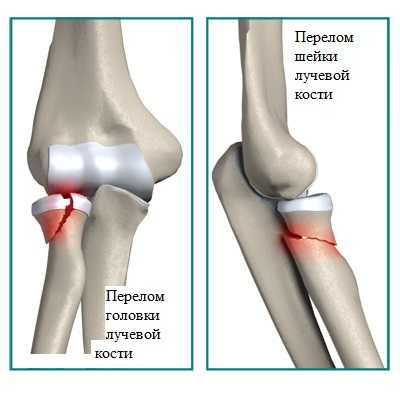

Показаниями к артроскопическому лечению могут быть: переломы головки лучевой кости, венечного отростка, головочки плечевой кости (головчатого возвышения).

Основная функция головки лучевой кости — это стабилизация локтевого сустава. При переломах головки или ее удалении появляются нестабильность и боль в локтевом суставе.

Венечный отросток играет большую роль в стабильности локтевого сустава. Травмы венечного отростка обычно сочетаются с повреждением связок.

• головки либо шейки лучевой кости возникает вследствие падения на прямую руку;

• венечного отростка возникает как следствие падения на согнутый локоть.